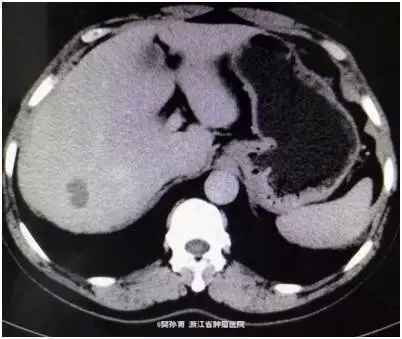

查体:心肺查体阴性,腹平软,无腹壁静脉曲张,全腹无压痛、反跳痛,腹部无包块。肝脏未触及,脾脏未触及,Murphy氏征阴性,肝、肾、脾无叩击痛,无移动性浊音。肠鸣音正常。 肿瘤标志物阴性。 CT表现:动脉期:肝包膜光整,肝脏形态正常,肝右叶可见低密度结节。大小约1.8*2.4 cm。边界模糊。门脉期:病灶强化幅度减低,边界较动脉期清晰。延迟期:病灶仍呈低密度。肝内胆管不扩张,肝门结构清晰自然,胆囊不大,壁光滑,腔内未见明显异常。脾脏、胰腺、胃、腹膜后未见明显异常。

初步诊断:肝脏占位,性质待查。 术中探查见于右肝后叶扪及一大约3x2.5 cm肿块,质硬,余肝未扪及异常,腹腔无肿大淋巴结,腹腔其它脏器未见异常。